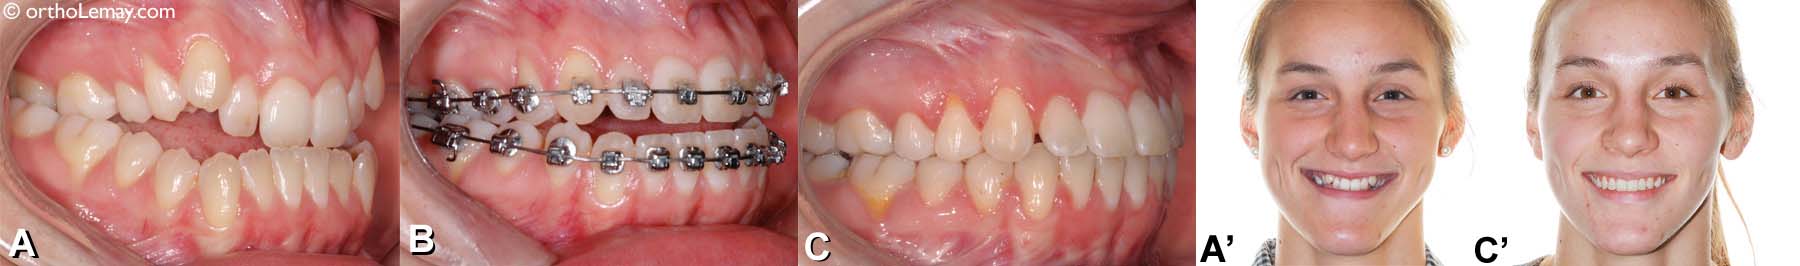

Chirurgie orthognathique bimaxillaire pour corriger une prognathie mandibulaire et déficience maxillaire. (A, A’) Malocclusion classe 3 et visage avant le traitement, (B) après les décompensations dentaires et avant la chirurgie, (C, C’) après les corrections chirurgicales (avancement maxillaire et recul mandibulaire). ➡ pour en savoir plus sur ce cas et voir d’autres malocclusions classe 3 traitées en ortho-chirurgie.